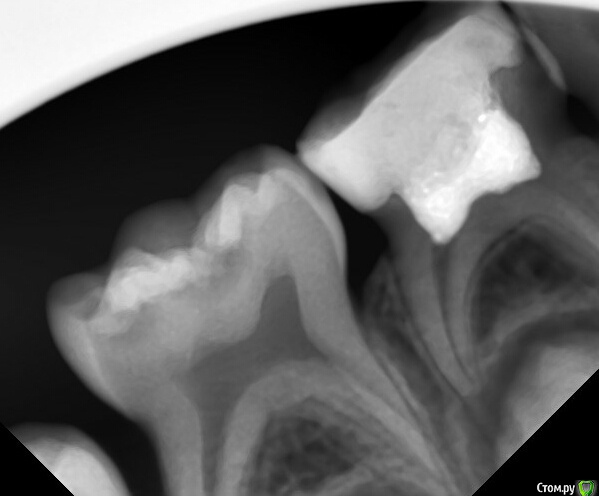

CRAZYDUCK Опубликовано 16 апреля, 2016 Поделиться Опубликовано 16 апреля, 2016 Я вот отказался от пульпотека, у меня были осложнения в виде полной резорбции корней, при условии герметичности. Пульпотек это формальдегид, соответсвенно он мумифицирует, а мумифицировать можно только мертвую ткань, а пульпа у нас живая. Я читал что полиоксиметилен(полиформальдегид), который входит в состав порошка коагулирует альбумины, тем самым вызывает поверхностную девитализацию, но на какую глубину он девитализирует? и до куда проникает формалин? как вообще это все работает? имхо он просто убивает зону роста, с последующей резорбцией корней, я пасс.Каждому свое ,crown, я не могу о пульпотеке плохо сказать,но несколько месяцев им не работаю ,перешла на рутдент быстротвердеющий (мта ),но перешла по след причинам -пульпотек очень резко пахнет (до слез в глазах ),и хочется что-то новое пробовать. Но работала пульпотеком почти 6 лет и результаты хорошие ,патологической резорбции не наблюдала,были осложнения очень давно ,но в тех случаях ,в которых реставрация большой полости сделана витремером ,он скалывался по контакту и тд.Прикрепляю только два снимка с пульпотеком ,наблюдения больше года ,снимки делала для диагностики "скрытого " кариеса на 5 ,поэтому корни не полностью у 4 . Но неплохих снимков с пульпотеком очень много Если несложно ,выложите с мта .интересно посмотреть . 2 Ссылка на комментарий